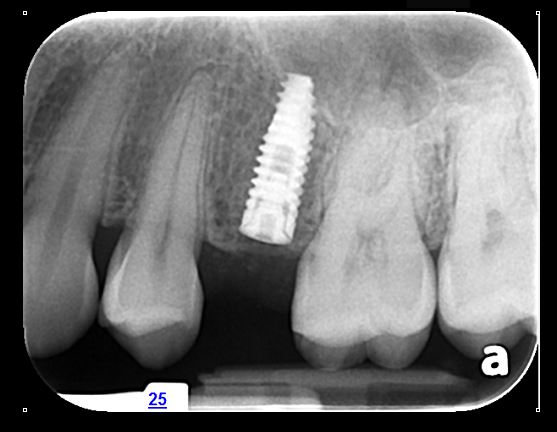

- CBCT: La tomografía computarizada de haz cónico es una imagen en 3D que proporciona imágenes de alta resolución del complejo craneofacial. Permite evaluar la cantidad y calidad ósea para la colocación de implantes dentales, adicionalmente es útil para la evaluación de dientes incluidos, fracturas y reabsorciones radiculares, entre otros.

La tomografía computarizada de haz cónico (CBCT) proporciona imágenes en 3D de alta resolución del craneofacial, ideal para planificar implantes, evaluar dientes incluidos, fracturas y reabsorciones radiculares.